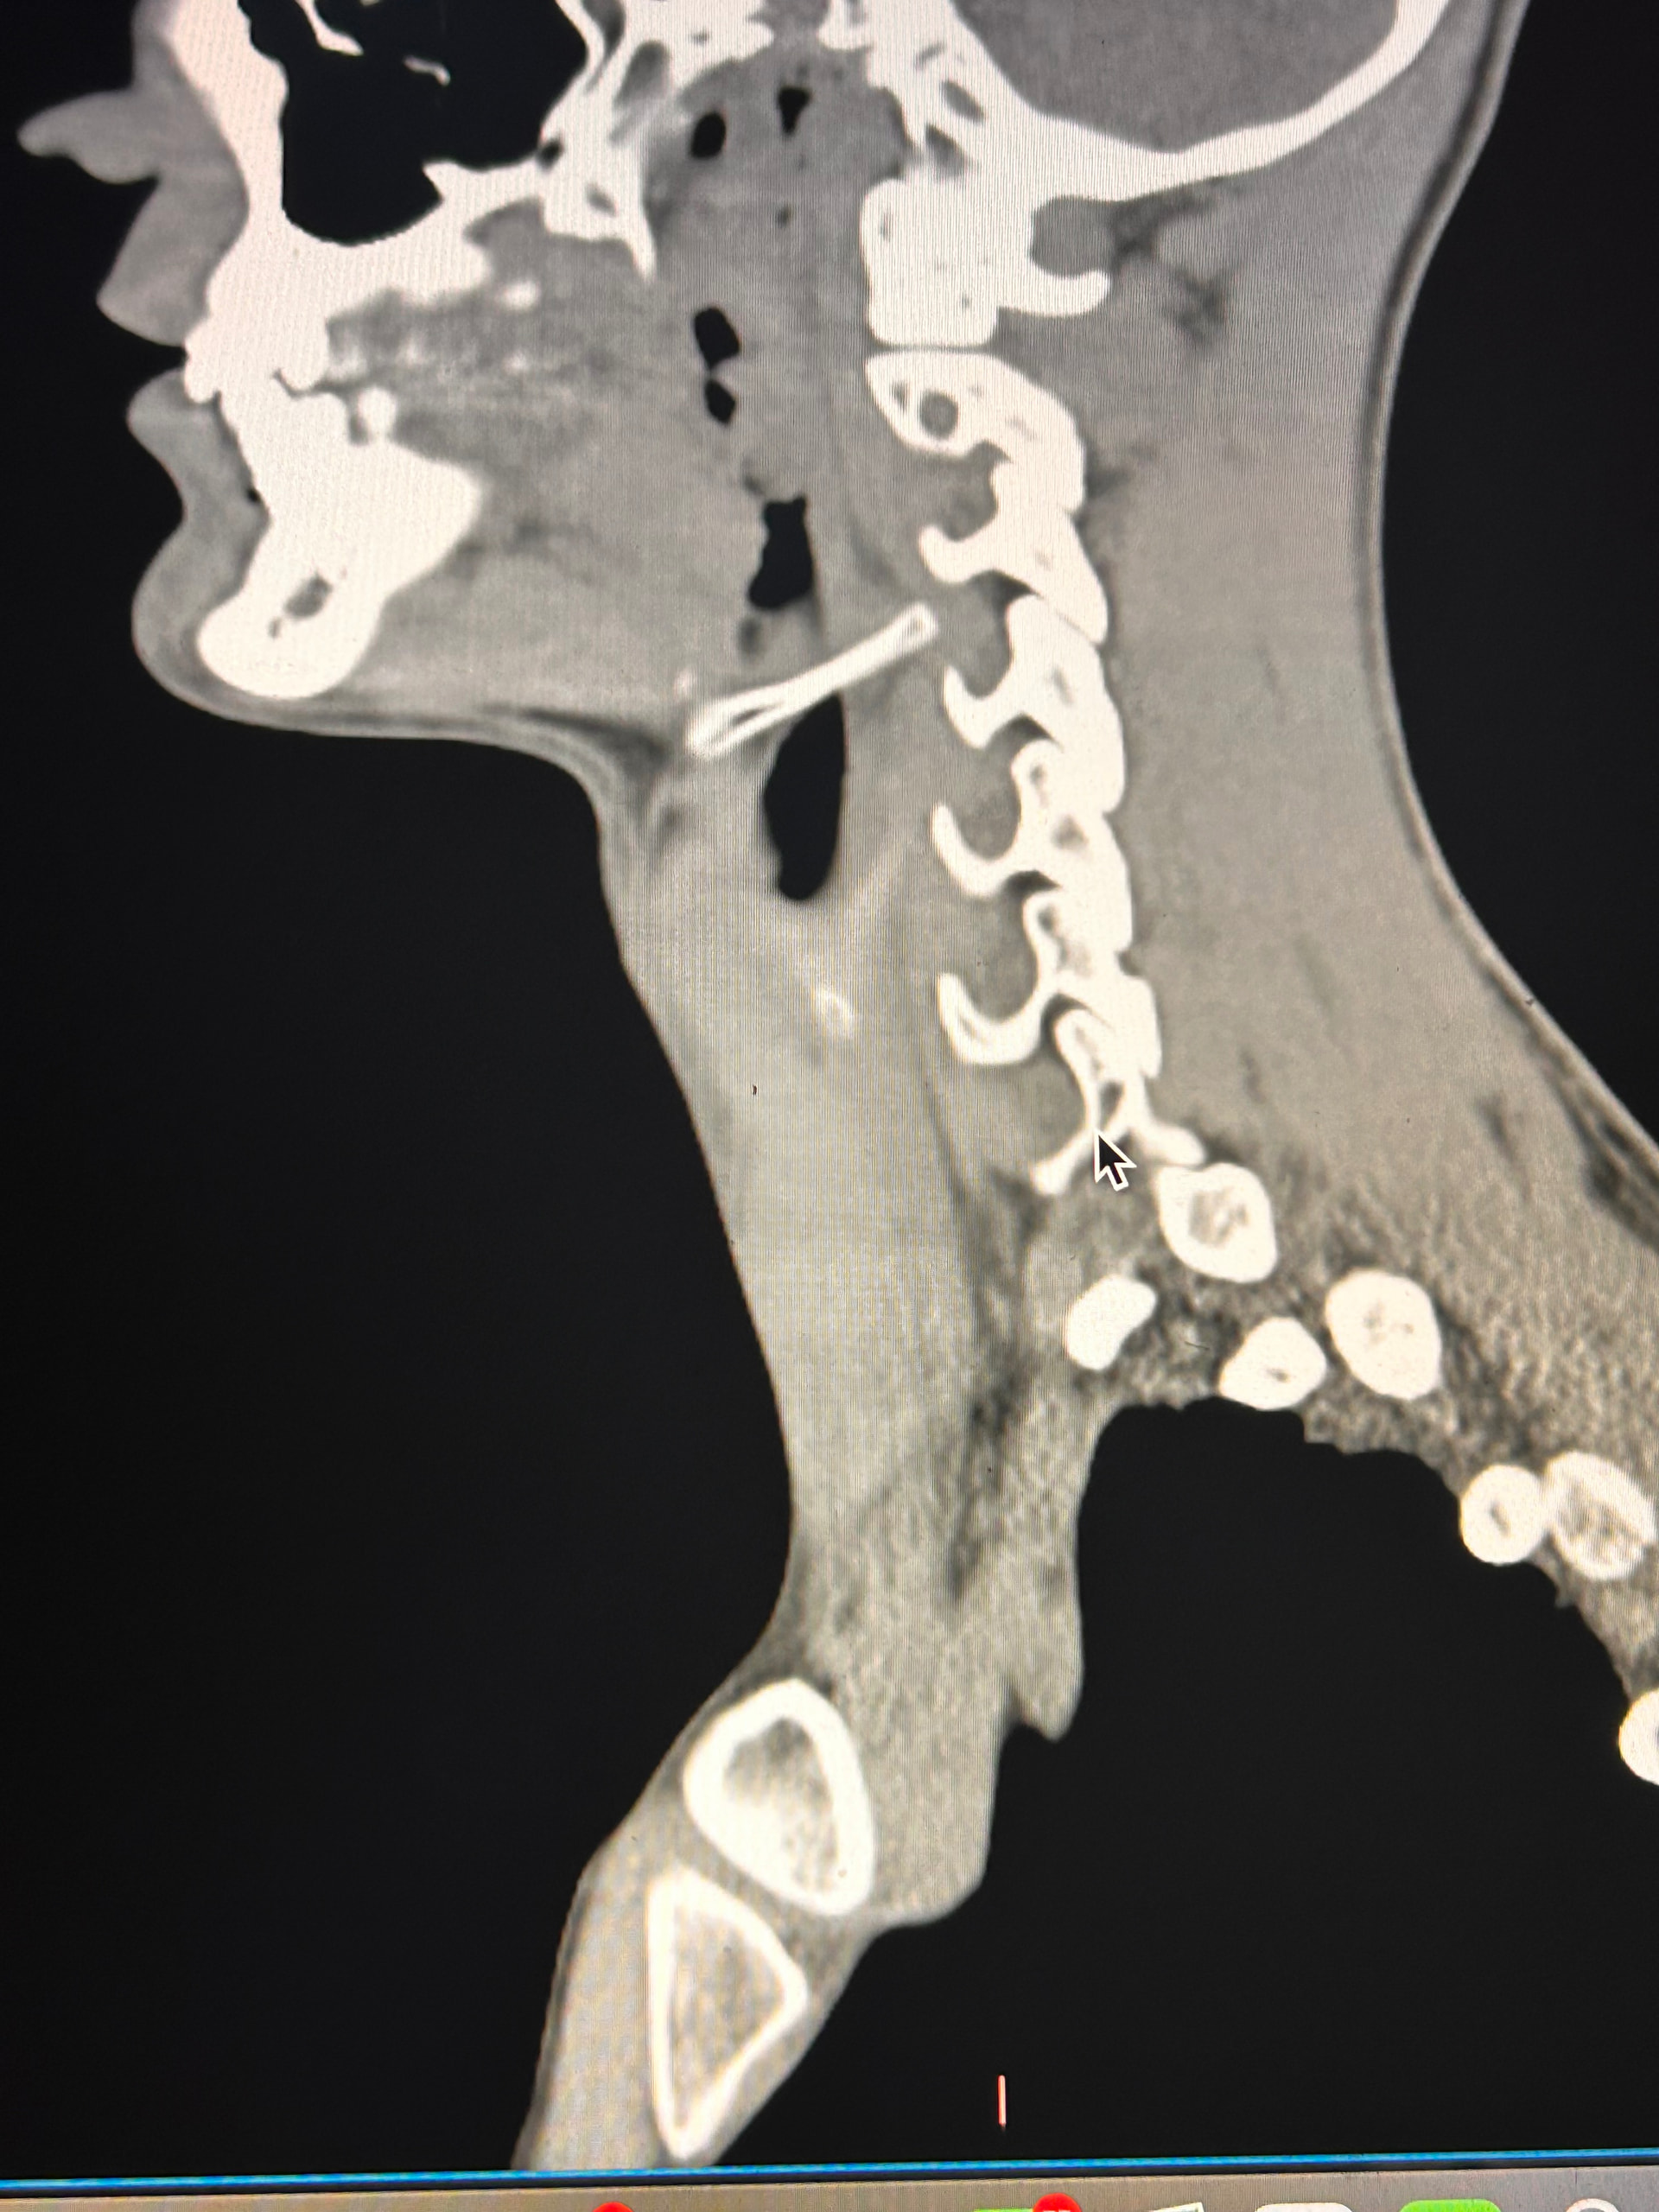

Here are some images of my 3-d ct, thanks for taking an interest it means a lot!

Oh and I almost forgot these were taken before I had my right styloidectomy

In this image of your left styloid, it appears from the angle of the picture that your left styloid is extremely close to the left transverse process of C1 (green circled area). If that’s truly the case, your left IJV is likely being squashed between the two & that means your vagus nerve is most likely being squashed at that point, too. Some of your symptoms could be vagal related. Also due to the angle of the image, it appears the greater horn of your hyoid could be very close to your spine which can cause internal/external carotid artery compression but can also cause symptoms that point to hyoid bone syndrome as you’ve suggested. Unfortunately, it doesn’t appear the CT scan was done w/ contrast as none of your veins or arteries appear in the images you posted & contrast is necessary to see those.

I’ll just add in as well that in your first image, the hyoid bone processes look pretty thick, more than you’d expect, so could well be part of your issues, but I do agree with @Isaiah_40_31 that your left styloid is very close to the C1 process, the right side looks a little longer than average… Also looking at the 1st & last images (I’m sorry, | can’t label them for you), there’s calcification below your hyoid which I’m presuming is the thyroid cartilage, it lookd pretty chunky compared to most people’s, so this could possibly be causing some issues too?

Here are some of my 2-d scans, thanks. The top one is my right greater horn and the bottom is the left

In this image, you can see the differences in the shapes of your hyoid’s greater horns. The right one is more curved but the left one is thicker in width medial to lateral. In this image from the front it looks like both greater horns may be contacting your cervical spine in certain head positions, but again, that may an illusion created by the angle of the image.

In the final two images you sent, the right greater horn is very close to your cervical spine so there’s a good chance it’s causing you some problems as well as possible carotid artery irritation or compression in different head positions. The image of the left one doesn’t show as much of the greater horn so I can’t tell how close to the spine it is. Can you back the left image out a bit so it looks more like the right one?

I was trying to get an image of the whole greater horn on the left but I could only get small glimpses of it as I went through the slides. Maybe because of its shape. As far as pain on the right that is where I usually notice issues, especially the lump I feel whenever I swallow, although the left can also get very tight and painful at times.